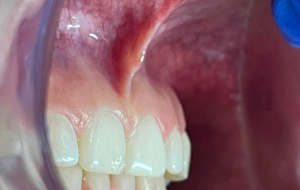

Frenillectomia Láser

En ocasiones se presenta en alguno pacientes un tejido fibroso denominado frenillo labial, dicha estructura anatómica es requerido retirarla en algunos casos cuando impide movimientos ortodónticos, o cuando afecta la encía del algún diente o cuando se desea liberar el labio y darle más movilidad y amplitud a la sonrisa. La Frenillectomia es el retiro de este tejido, En nuestro consultorio lo realizamos mediante cirugía laser que evita infecciones, cicatriza sin necesidad de suturas y la anestesia requerida es mínima, siendo mucho más cómoda para niños, adolescentes y personas nerviosas.